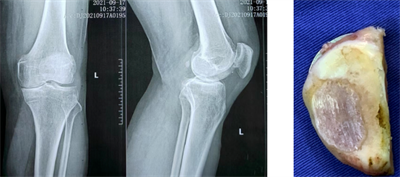

(图示膝前内侧骨关节炎X线及术中情况)